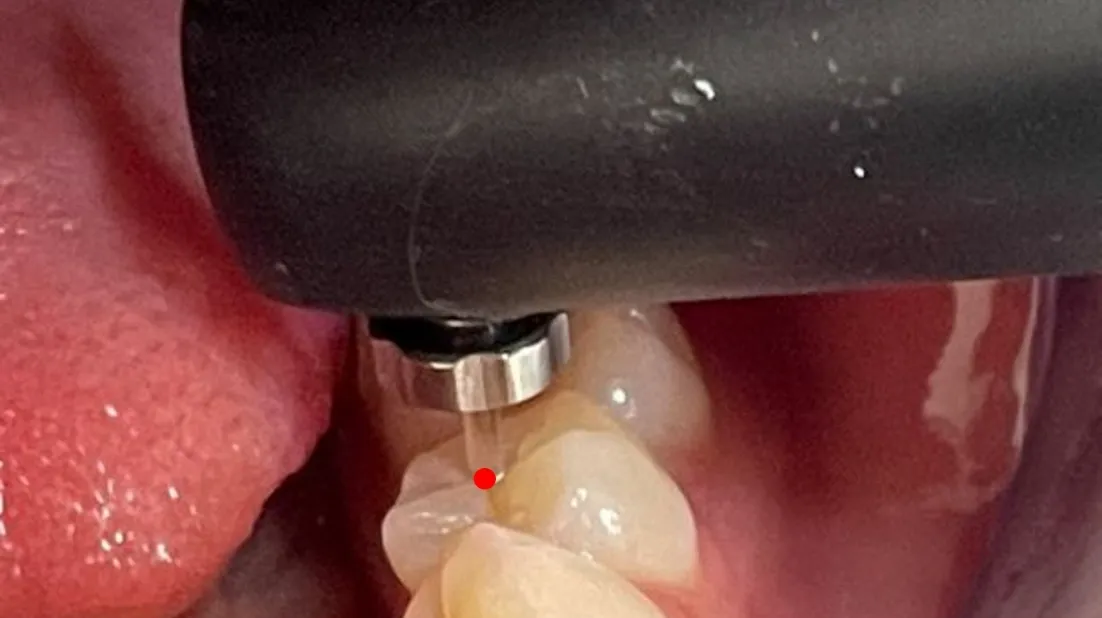

レーザー光を使ったむし歯診断機器(ダイアグノデント)を使用する様子

まずレーザー光を使ったむし歯診断機器(ダイアグノデント)を使用して、むし歯が削るべきでないエナメル質内に留まっている状態なのか(初期むし歯)、それとも削って除去すべき象牙質まで進行しているのかを見極めます。

ダイアグノデントでは、むし歯の進行度を100段階で評価することが可能です。